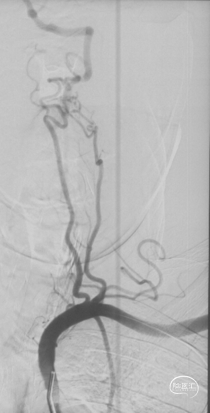

CTA和DSA

CTA和DSA所见:双侧颈内动脉闭塞,右侧椎动脉发出PICA后闭塞,左侧椎动脉V1-V2段闭塞。两条健壮的侧枝通过肌支吻合汇入左椎动脉V2段,构成了整个大脑大部分供血的主要来源。双侧颈外动脉亦有少量血流供应颅内。这样的颅内供血很容易发生失代偿,导致TIA甚至脑梗。